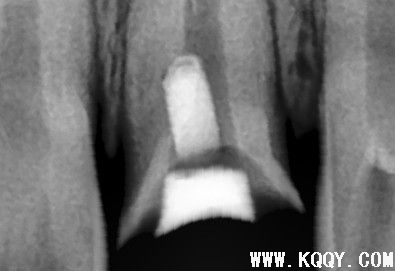

根管侧穿MTA修补

核心提示:根管侧穿MTA修补